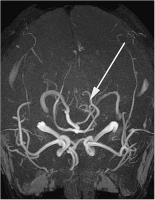

Abbildung 2: Initiale Magnetresonanzangiographie (MRA): Hinweis auf eine arteriovenöse Malformation (AVM) der Arteria cerebelli superior links.

MRA